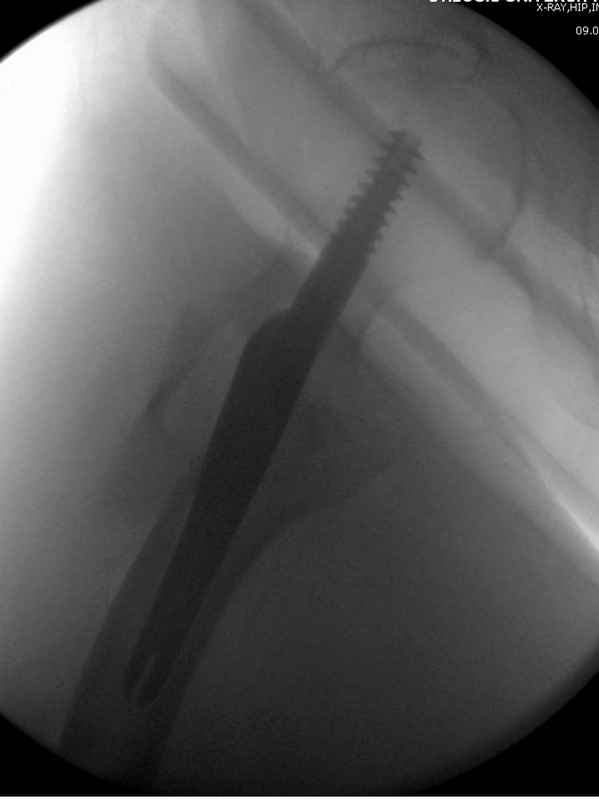

[Ortho] Чрезвертельный перелом бедра

Здесь 83 года, травма в результате падения

Имя     : #6 IT fx  introp.jpg